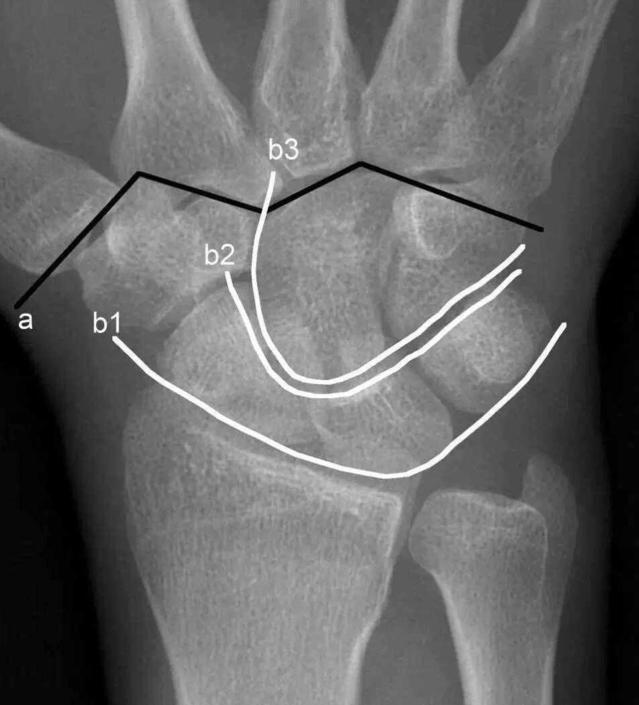

3影像学上,可以用Gilula线评价桡腕及腕中关节,如此弧线平滑、无中断,说明各腕骨位置关系正常,否则提示有异常

X线正位片中,Gilula线中断则提示腕关节异常

各腕骨间隙大于等于2mm,且与健侧不同,提示异常